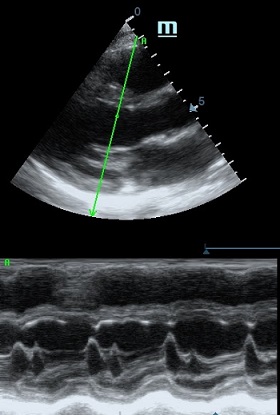

TAPSE - показатель амплитуды движения латеральной части кольца трикуспидального клапана, позволяет количественно и быстро оценить систолическую функцию правого желудочка, норма которого составляет более 17 мм. Главным условием является проведение линии М-режима параллельно стенке правого желудочка в апикальном четырех камерном сечении, что легко достигается при Free Xros.